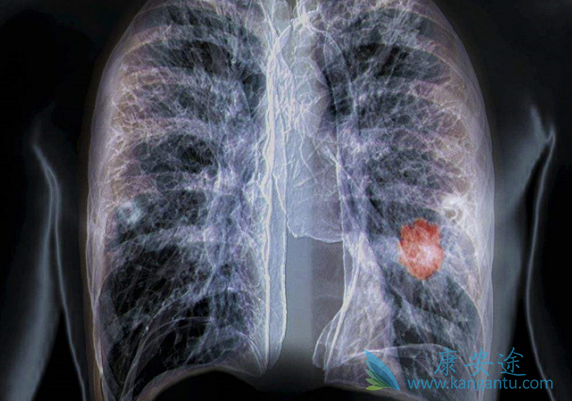

当然肺癌患者也会痰中带血。肺癌早期症状主要包括:咳嗽、血痰、声音嘶哑、气促和麻木。那肺癌患者痰中带血是怎么回事呢?引发肺癌患者痰中带血的主要原因包括下呼吸道病变,消化道病变和咽部病变或肿瘤浸润肺部毛细血管。当发现肺癌痰中带血时,首先不能惊慌失措,应尽快检查找出原因,再对症下药施治。痰中带血并不一定是肺癌。